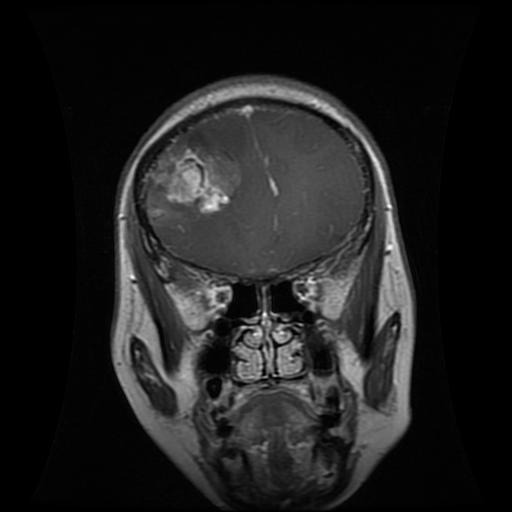

A guide on how to tune convolutional neural networks for image classification. The python walkthrough details how to build a MRI classifier to accurately distinguish between gliomas, meningioma, pituitary and non-tumour samples.